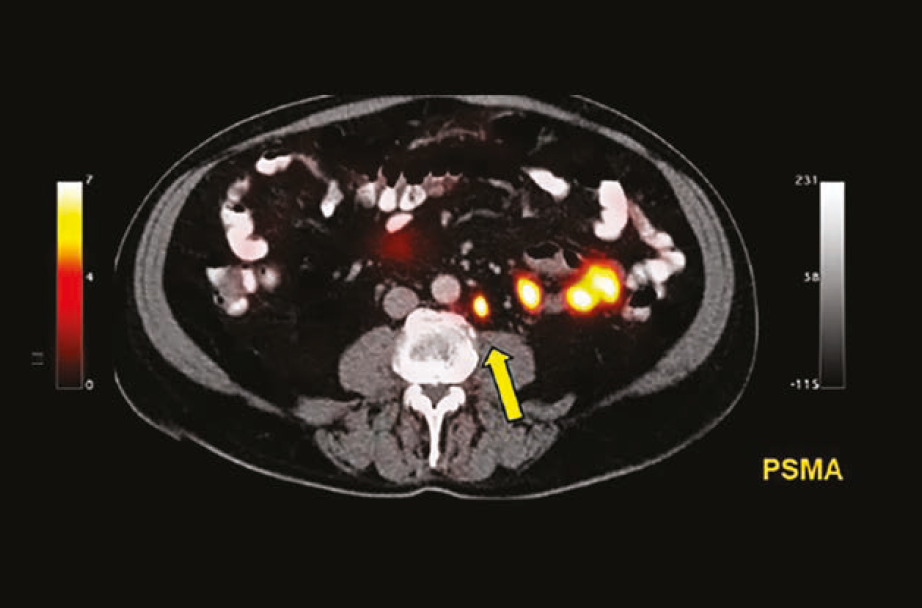

Murphy shares the backstory of how PSMA PET/CT imaging has emerged as a major advancement in the prostate cancer armamentarium.

The new drug application for 18F-DCFPyL is supported by results from the OSPREY and CONDOR trials.